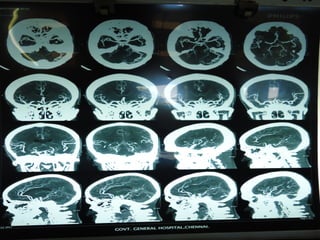

41 yr old saravanan was admitted with  c/o vomiting 1 episode,altered sensorium and difficulty in walking since morning.no h/o of trauma  Not a k/c DM ,SHT. Not a smoker/alcoholic o/e irritable nystagmus+,pooling of saliva+,9 th  and 10 th  N palsy,b/l plantar withdrawal BP-120/80mm Hg

Investigations  Echo normal Coagulation profile normal Homocysteine level slight increase

Imaging: AV Malformation